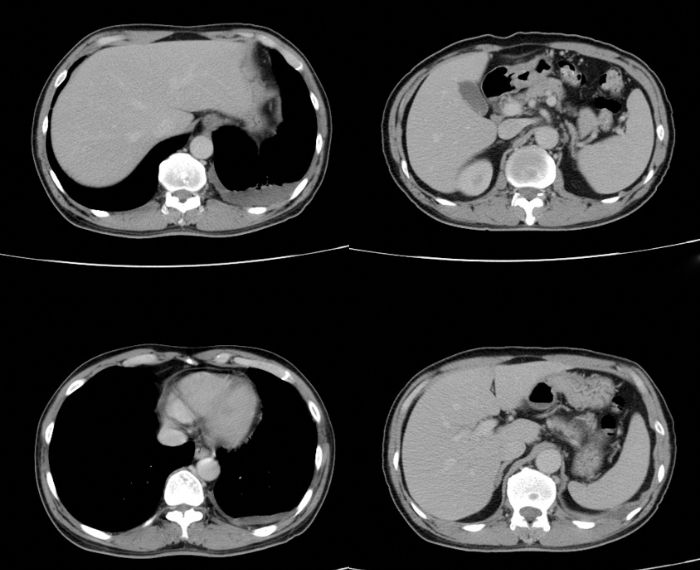

Lung Cysts (Hydatid Cyst)

What is a hydatid (lung) cyst? Lung cysts, also known as hydatid cysts, are